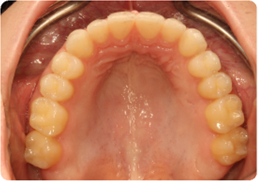

Each case shows the front view and an arch or side view, before and after BioLign Method-guided treatment.

Overlapping teeth resolved through arch form restoration